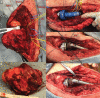

Case presentation: We report a case of a 70-year-old male with periosteal chondrosarcoma of the proximal humerus who underwent margin-negative resection and reverse total shoulder endoprosthetic reconstruction that was complicated by glenosphere dissociation sustained from falling onto a hyperflexed arm. Successful revision arthroplasty was performed.